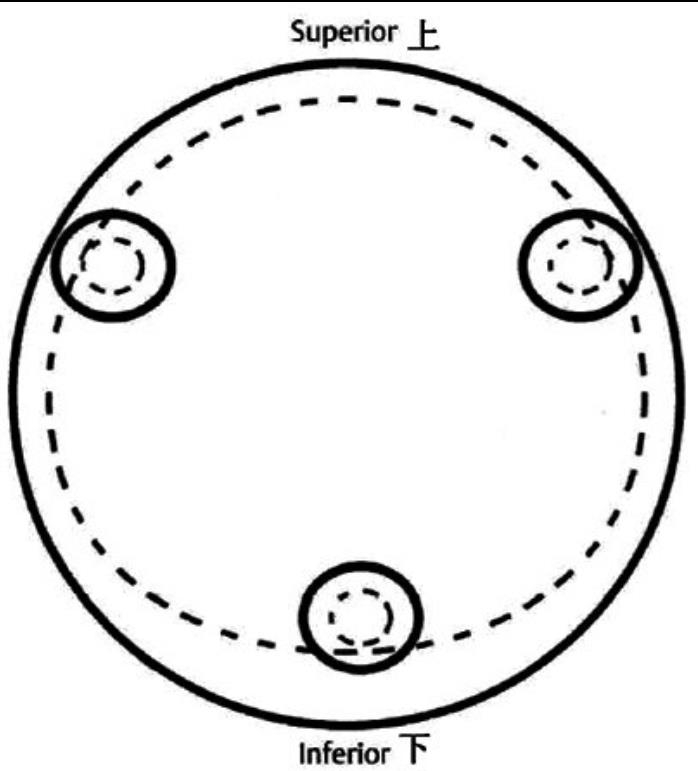

2、标准放置螺钉为倒三角形,其中下方螺钉在股骨矩,后方螺钉在后方骨皮质、研究发现倒三角形平行三枚螺钉能提供最佳的固定强度;

空心钉固定的三原则:“贴边、平行、倒品”。

1、贴边是指3枚螺钉在股骨颈内,尽量靠近外围皮质。这样3枚螺钉作为一个整体,对整个骨折面可形成面状加压,如果3枚螺钉不够离散,更趋于点状加压,稳定性较差,不能较好地对抗扭转和剪切。

图1 3枚螺钉在股骨颈内的理想位置